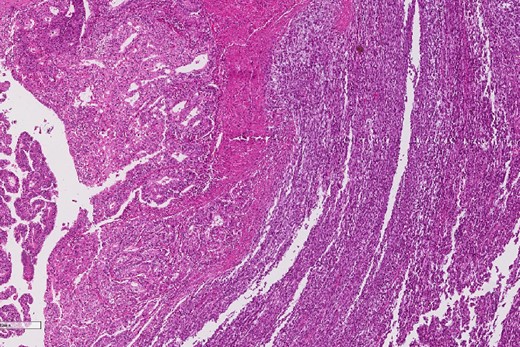

A review of the previously resected esophageal tumor revealed the presence of both epithelial and sarcomatous components. The epithelial component was composed of moderately to poorly differentiated adenocarcinoma, while the sarcomatous component showed hyperchromatic round to spindle cells with scant cytoplasm and frequent mitoses (Figs 3–6). The intrathoracic tumor showed a similar morphology as the sarcomatous component of the esophageal tumor, with focal rhabdomyoblastic differentiation (Fig. 7). The latter was strongly positive for desmin, myogenin, and MyoD1 and was focally positive for synoplastin, CD56, CD 10, and FL1.

The epithelial component of the esophageal tumor is composed of moderately to poorly differentiated adenocarcinoma.